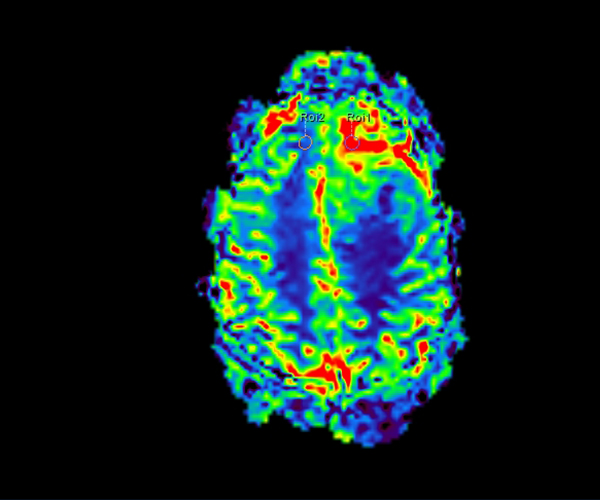

L’augmentation de l’effet de susceptibilité magnétique à plus haut champ permet d’améliorer la détection des hémorragies et est utilisé également dans l’imagerie de perfusion (tumeurs) et l’IRM fonctionnelle (BOLD). L’allongement du T1 à plus haut champ entraîne une meilleure saturation des tissus statiques et par conséquent une augmentation du contraste sang/tissus dans l’AngioIRM.

La séquence de perfusion par marquage des spins artériels (ASL) étudiant la perfusion cérébrale sans injection trouve pleinement son application à 3T dans la pathologie vasculaire, la caractérisation et le suivi post-thérapeutique des lésions tumorales, les démences et certaines pathologies psychiatriques.